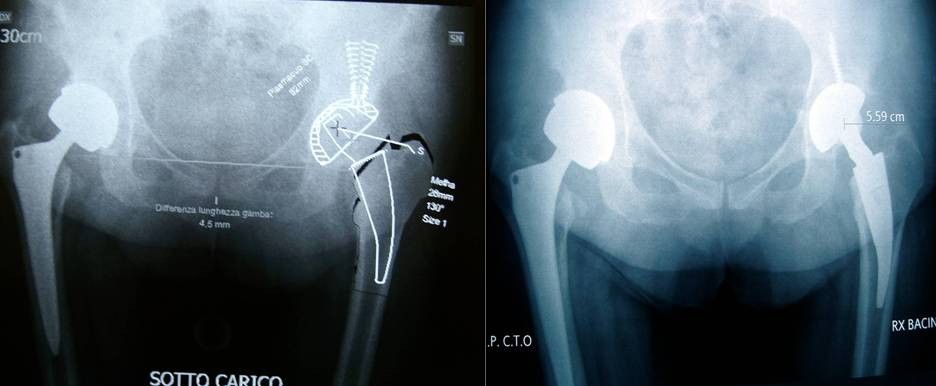

Artroprotesi

Anca

L’intervento di artroprotesi di anca è unanimemente riconosciuto come uno degli interventi ortopedici con più successo ed in grado di garantire un immediato beneficio al paziente.